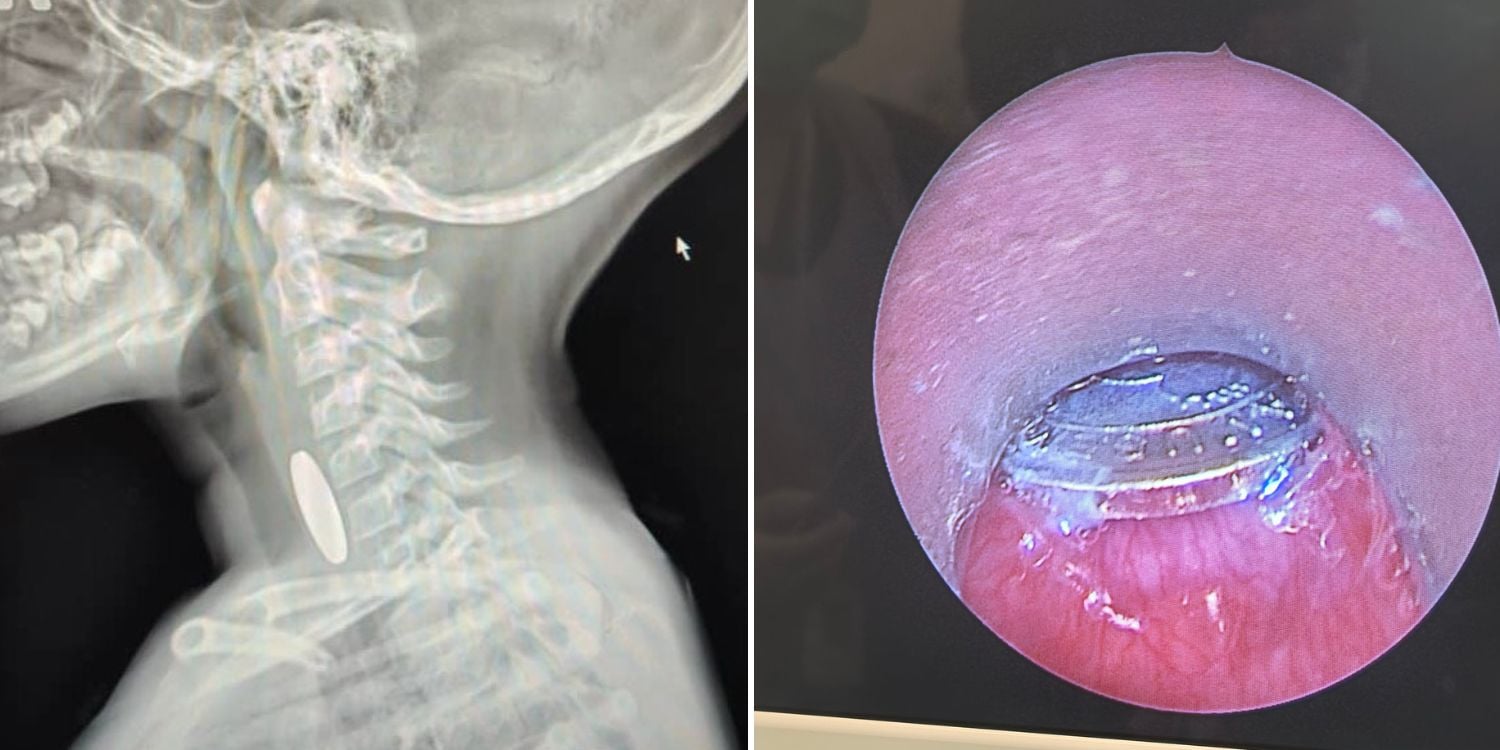

A child in Malaysia underwent emergency surgery after accidentally swallowing an arcade token.

Dr Mohd Shaiful Nizam, a head and neck surgeon at a hospital in Pahang state, said he was on duty last Saturday (15 March) night when he had to rush to the operating theatre.

He was called to remove a “foreign body” from a child’s oesophagus.

He initially assumed it was a swallowed coin as an X-ray showed a coin-shaped object lodged in the child’s oesophagus.

However, during the procedure, he was puzzled to discover that the foreign object didn’t look like a coin.

The realisation that it was an arcade token took him by surprise.

This was the first time he’d encountered a case like this, he said.

Thankfully, the surgery went smoothly, he added.